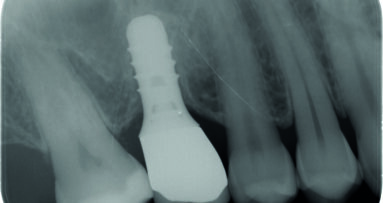

Paziente di 40 anni in buono stato di salute non fumatore si presenta alla mia attenzione con dolore alla pressione in zona 16 dove anni prima era stato ...